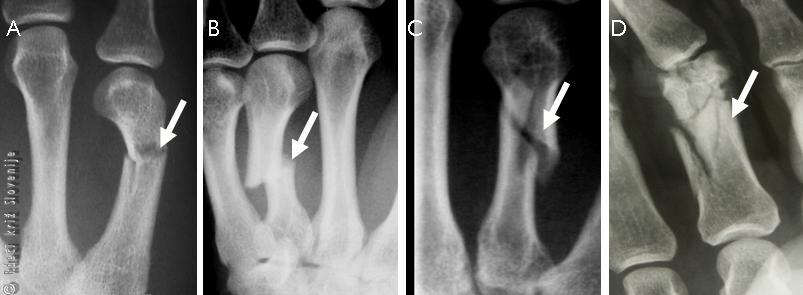

Slika 11

Stresni zlom diafize pete stopalnice.

Slika 17

Konzervativno zdravljenje.

A – RTG slika ki pokaže zlom osnovnega členka mezinca desne noge(puščica).

B – Obližna imobilizacija k sosednjemu prstu.

C – Spremenjena oblika podlahti pri zlomu.

D – RTG slika, ki pokaže zlom koželjnice.

E – Naravnava in zamavčenje v splošni anesteziji.

F – Doramenski mavec.